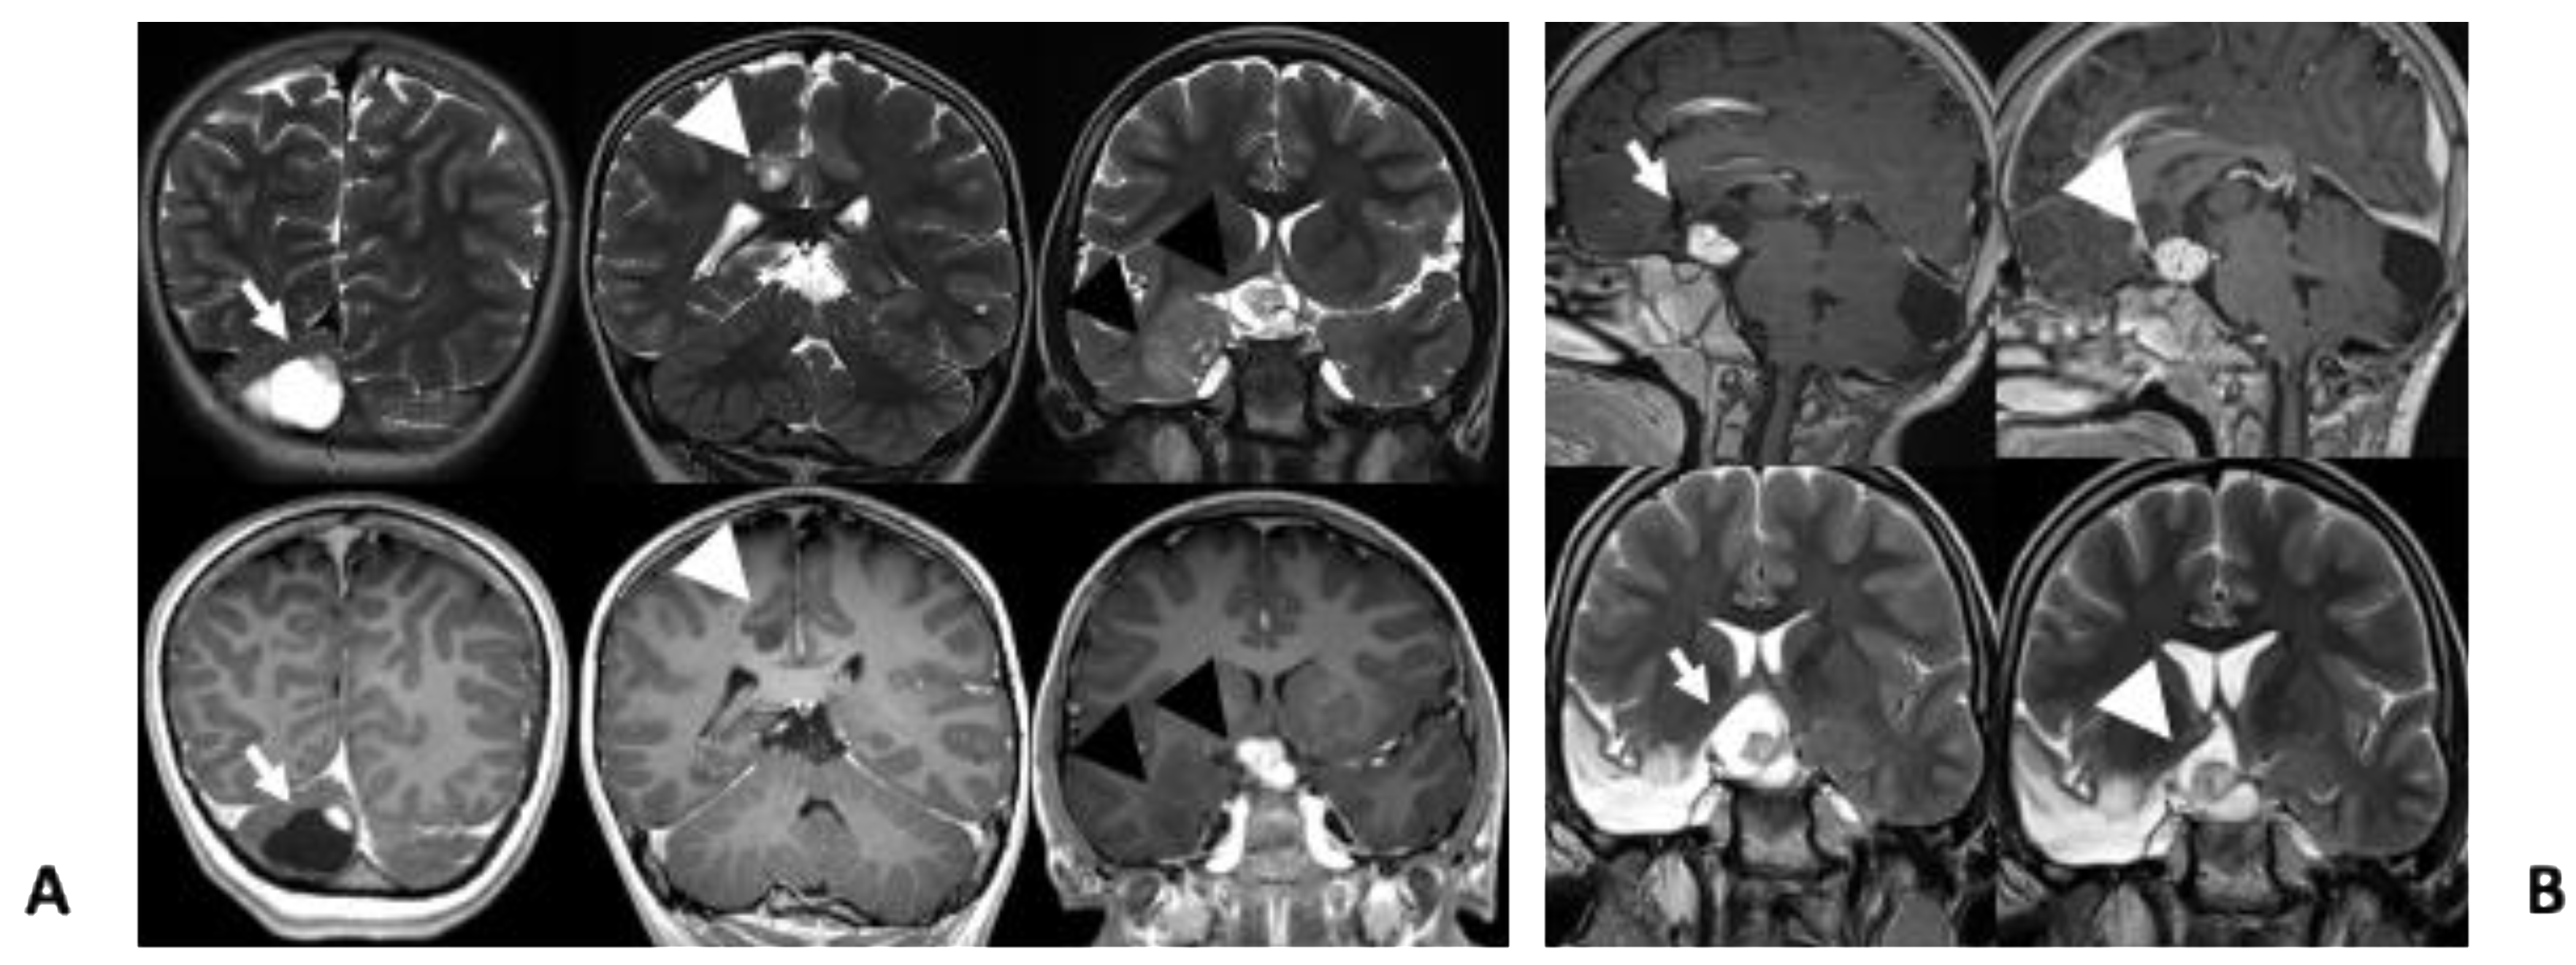

| 30 | Our case | 9 | F | PTPN11 c.922A > G; p.Asn308Asp | Pilocytic astrocitoma and glioneuronal tumor | Cerebellum Right temporal lobe |